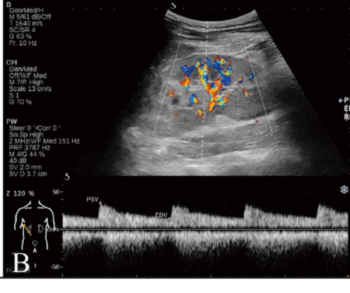

In order to facilitate optimal detection and assessment of liver fibrosis and steatosis, the newly launched Hepatus 6 Diagnostic Ultrasound System offers the capabilities of real-time two-dimensional ultrasound with visual transient elastography in one device.